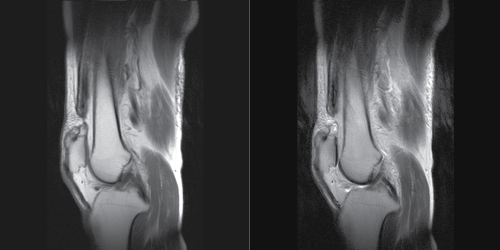

A 72-year-old man injured both knees after he slipped off a step. He was unable to stand up afterward and went to a clinic where his injury was diagnosed radiographically as contusions of both knees accompanied by muscle weakness. Five days later, clinical examination in our hospital showed a supra-patellar gap (Figure 1), moderate hemarthrosis of both knees, and failure of active knee extension. Based on this, the patient was diagnosed with bilateral rupture of the quadriceps tendons. Magnetic resonance imaging (MRI) confirmed the diagnosis, showing the quadriceps tendon rupture at the osteotendinous junction (Figure 2). Radiographs of his knees revealed the delle in the suprapatellar soft tissue, low-riding patella [3] and an avulsion fragment on the patella (Figure 3). The patellar heights of his right and left knees were 0.89 and 0.68, respectively, using the Insall-Saivati method. He did not have concomitant diseases.

Figure 2: MRI on sagittal plane of Case 1. a) Proton density-weighted sequences; b) T2 weighted image.

MRI is generally accepted as the most satisfactory way to diagnose tendon rupture. MRI can reveal not only the rupture but also the location of the injury site such as the osteotendinous junction or the musculotendinous area [10]. Therefore, MRI is used for diagnosis and also for preoperative planning [11]. Ultrasound is reported as a rapid way to investigate tendon rupture, which is a highly sensitive and specific means of assessment [12]. It is reported that Ultrasound can describe the location of the rupture and help differentiate complete from partial tears.